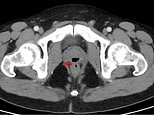

The CT scan has a small arrow pointing to a small tunnel that developed between the patient’s anus and prostate, allowing faeces to come out in his urine and for semen and urine to come out of his anus

They discovered the patient was suffering from the problem after a CT scan of his pelvis revealed he had a ‘gas-filled structure’ linking his prostate and rectum.